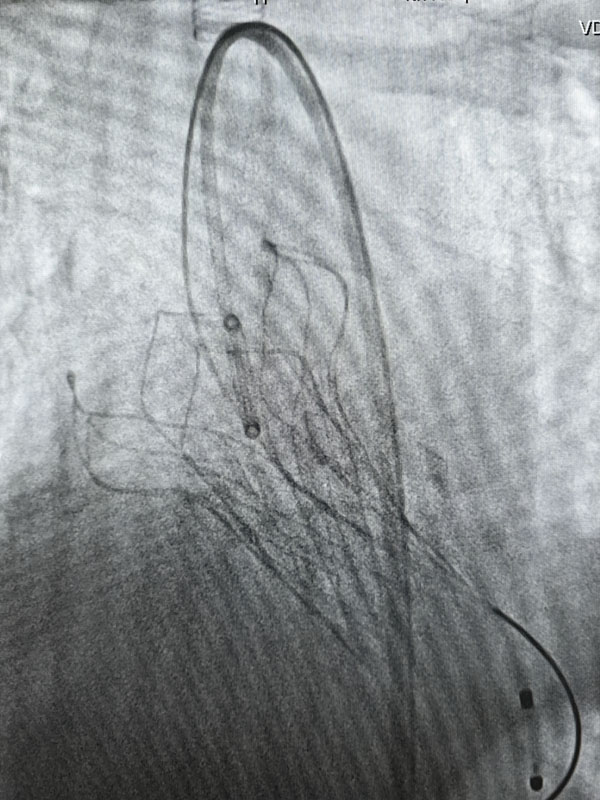

經過充分的術前準備,兩臺手術由心血管外科趙永波副主任主刀,趙偉超主治醫師、侯五輝主治醫師密切配合,選擇經皮股動脈穿刺,預埋縫合器,術中反復造影,準確定位釋放瓣膜,術后造影及超聲提示人工瓣膜開啟功能良好。為確保術中安全,體外循環小組全程保駕護航。患者生命體征平穩,術后一日均轉出監護室。